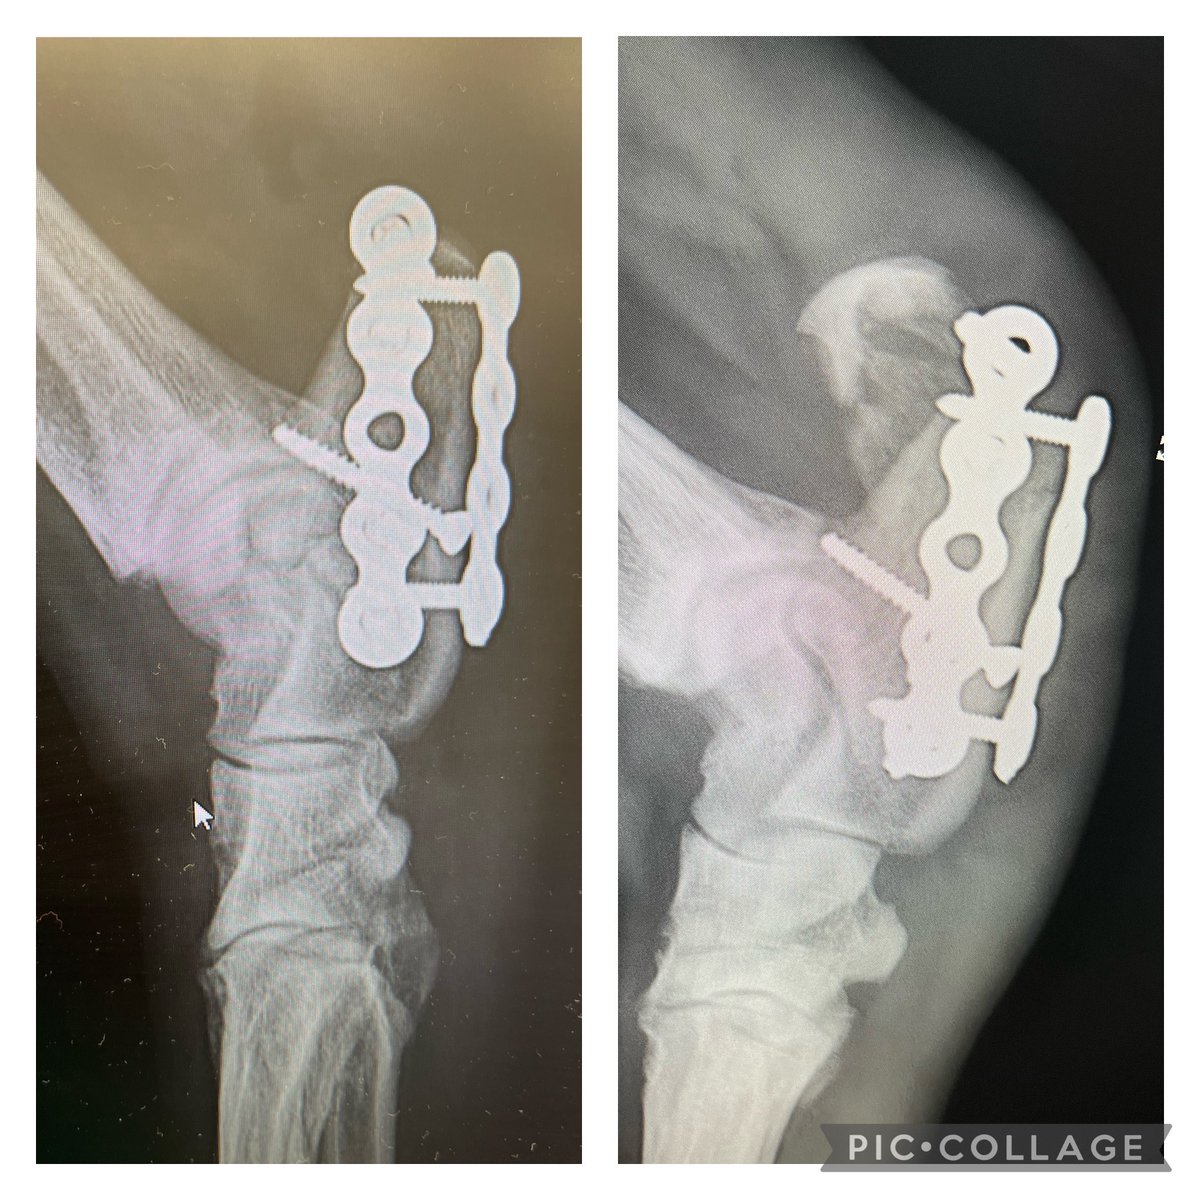

Challenging case? We'd love to have some of you share your challenging revision cases with us in Bristol. Can be anonymous if required ;-) More details here bvoa.co.uk/events/bvoa-au…